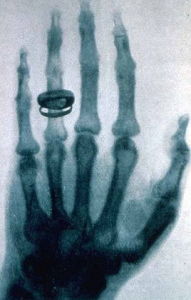

1895年德國物理學家威廉·康拉德·倫琴發現X 射線(一般稱 X 光)以來,開啟了醫學影像嶄新的一頁,在此之前,醫師想要了解病患身體內部的情況時,除了直接剖開以外,就只能靠觸診,但這兩種方法都有一定的風險。1978年,應該放射學年會上,一位名叫G.N.Hounsfield的工程師公布了計算機斷層攝影的結果。這是繼X射線發現後,放射醫學領域裡最重要的突破,也是20世紀科學技術的重大成就之一。Hounsfield與Cormack由於在放射醫學中的劃時代貢獻而獲得了1979年的諾貝爾生理與醫學獎。超聲成像設備的發展得益於在第二次世界大戰中雷達與聲納技術的發展。在20世紀50年代,簡單的A型超聲診斷儀開始用於臨床。到了70年代,能提供斷面動態的B型儀器問世。80年代初問世的超聲彩色血流圖(color flow mapping,CFM)是目前臨床上使用的高檔超聲診斷儀。1945年美國學者首先發現了磁共振現象,從此產生了核磁共振譜學這門科學。70年代後期,對人體的磁共振成像獲得成功。2003年,諾貝爾勝利或醫學獎授予了對磁共振成像研究做出了傑出貢獻的美國科學家Paul C.Lauterbur和應該科學家Peter Mansfied。